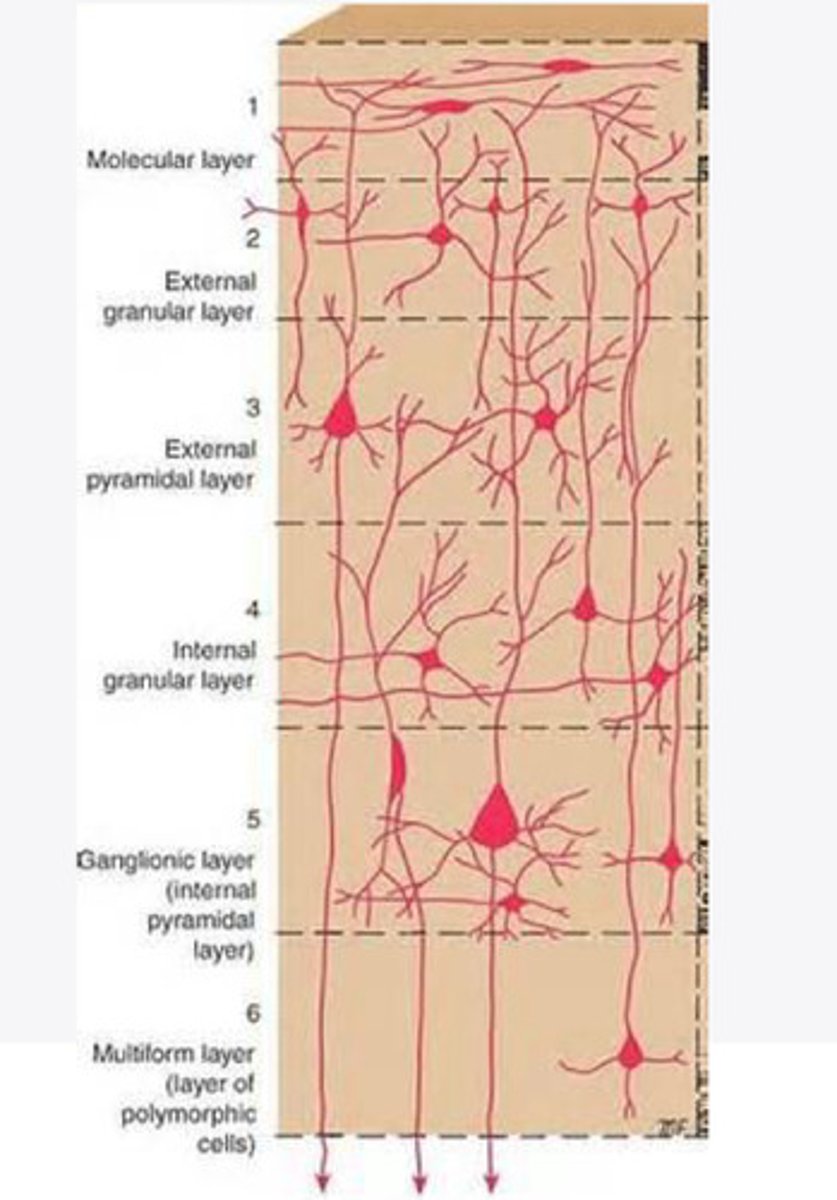

divided into 6 distinct layers, due to varying densities of cell body types within each layer

The cortex of the brain is divided into how many layers? Why is it divided into layers?

Layers of the cortex of the brain pic

2 and 4

What are the layers of the cortex that are associated with input?

3 and 5

What are the layers of the cortex that are associated with output?

molecular layer

What is the name of Layer 1 of the cortex of the brain?

very few cells

Does Layer 1 of the cortex have a lot or few cells?

receives dendrites from internal layers so it may actually function as a coordinating center where layers can communicate action

What does Layer 1 of the cortex do?

1

Every layer sends densities to Layer ____?

1

What layer serves as the "water cooler" of the brain?

external granular layer

What is the name for layer 2 of the cortex of the brain?

receives input from other cortical regions

What is the function of Layer 2 of the Cortex of the brain?

Stellate

What type of cells (stellate/pyramidal) would be most concentrated in Layer 2?

external pyramidal layer

What is the name for layer 3 of the cortex of the brain?

sends output to the other cortical layers

What is the function of Layer 3 of the cortex of the brain?

pyramidal

What type of cells (stellate/pyramidal) would be most concentrated in Layer 3 of the brain?

Layers 2 and 3

What layers are associated with association and commissural fibers?

Layer 3 - axons of cell bodies

Layer 2 - synapse into target areas in Layer 2

What part of the axons is in Layer 2/ in layer 3?

Layer 3 - external pyramidal layer

All axonal cel bodies for association and commissural fibers lie within what layer of the Cortex of the brain?

internal granular

** or called the striate cortex because it is so thick that you can see a line through this layer even in unstrained brain slides

What is the name for the 4th layer of the cortex of the brain?

receives input from the thalamus, geniculocortical layer, and other brainstem areas

What is the function for the 4th layer of the Cortex of the brain?

very thick within the vision, auditory, and somatosensory areas

Is Layer 4 thick or thin within SENSORY areas of the cortex?

Internal pyramidal

What is the name for Layer 5 of the cortex of the brain?

sends axons to the brainstem (corticobulbar) and spinal cord (corticospinal)

What is the function of Layer 5 of the cortex of the brain?

in motor areas of the cortex?

Where is layer 5 very thick in the brain?

the frontal lobe -- very motor heavy

What lobe of the brain will have a thick layer 5 of the cortex of the brain?

the multiform layer

What is the name of layer 6 of the cortex of the brain?

-sends axons back to the thalamus through corticogeniculate fibers

-modulates what information the thalamus sends to the cortex to control the strength of the signal received and modulate what you pay attention to

What is the function of layer 6 of the cortex of the brain?

no

Is layer 6 a motor layer?